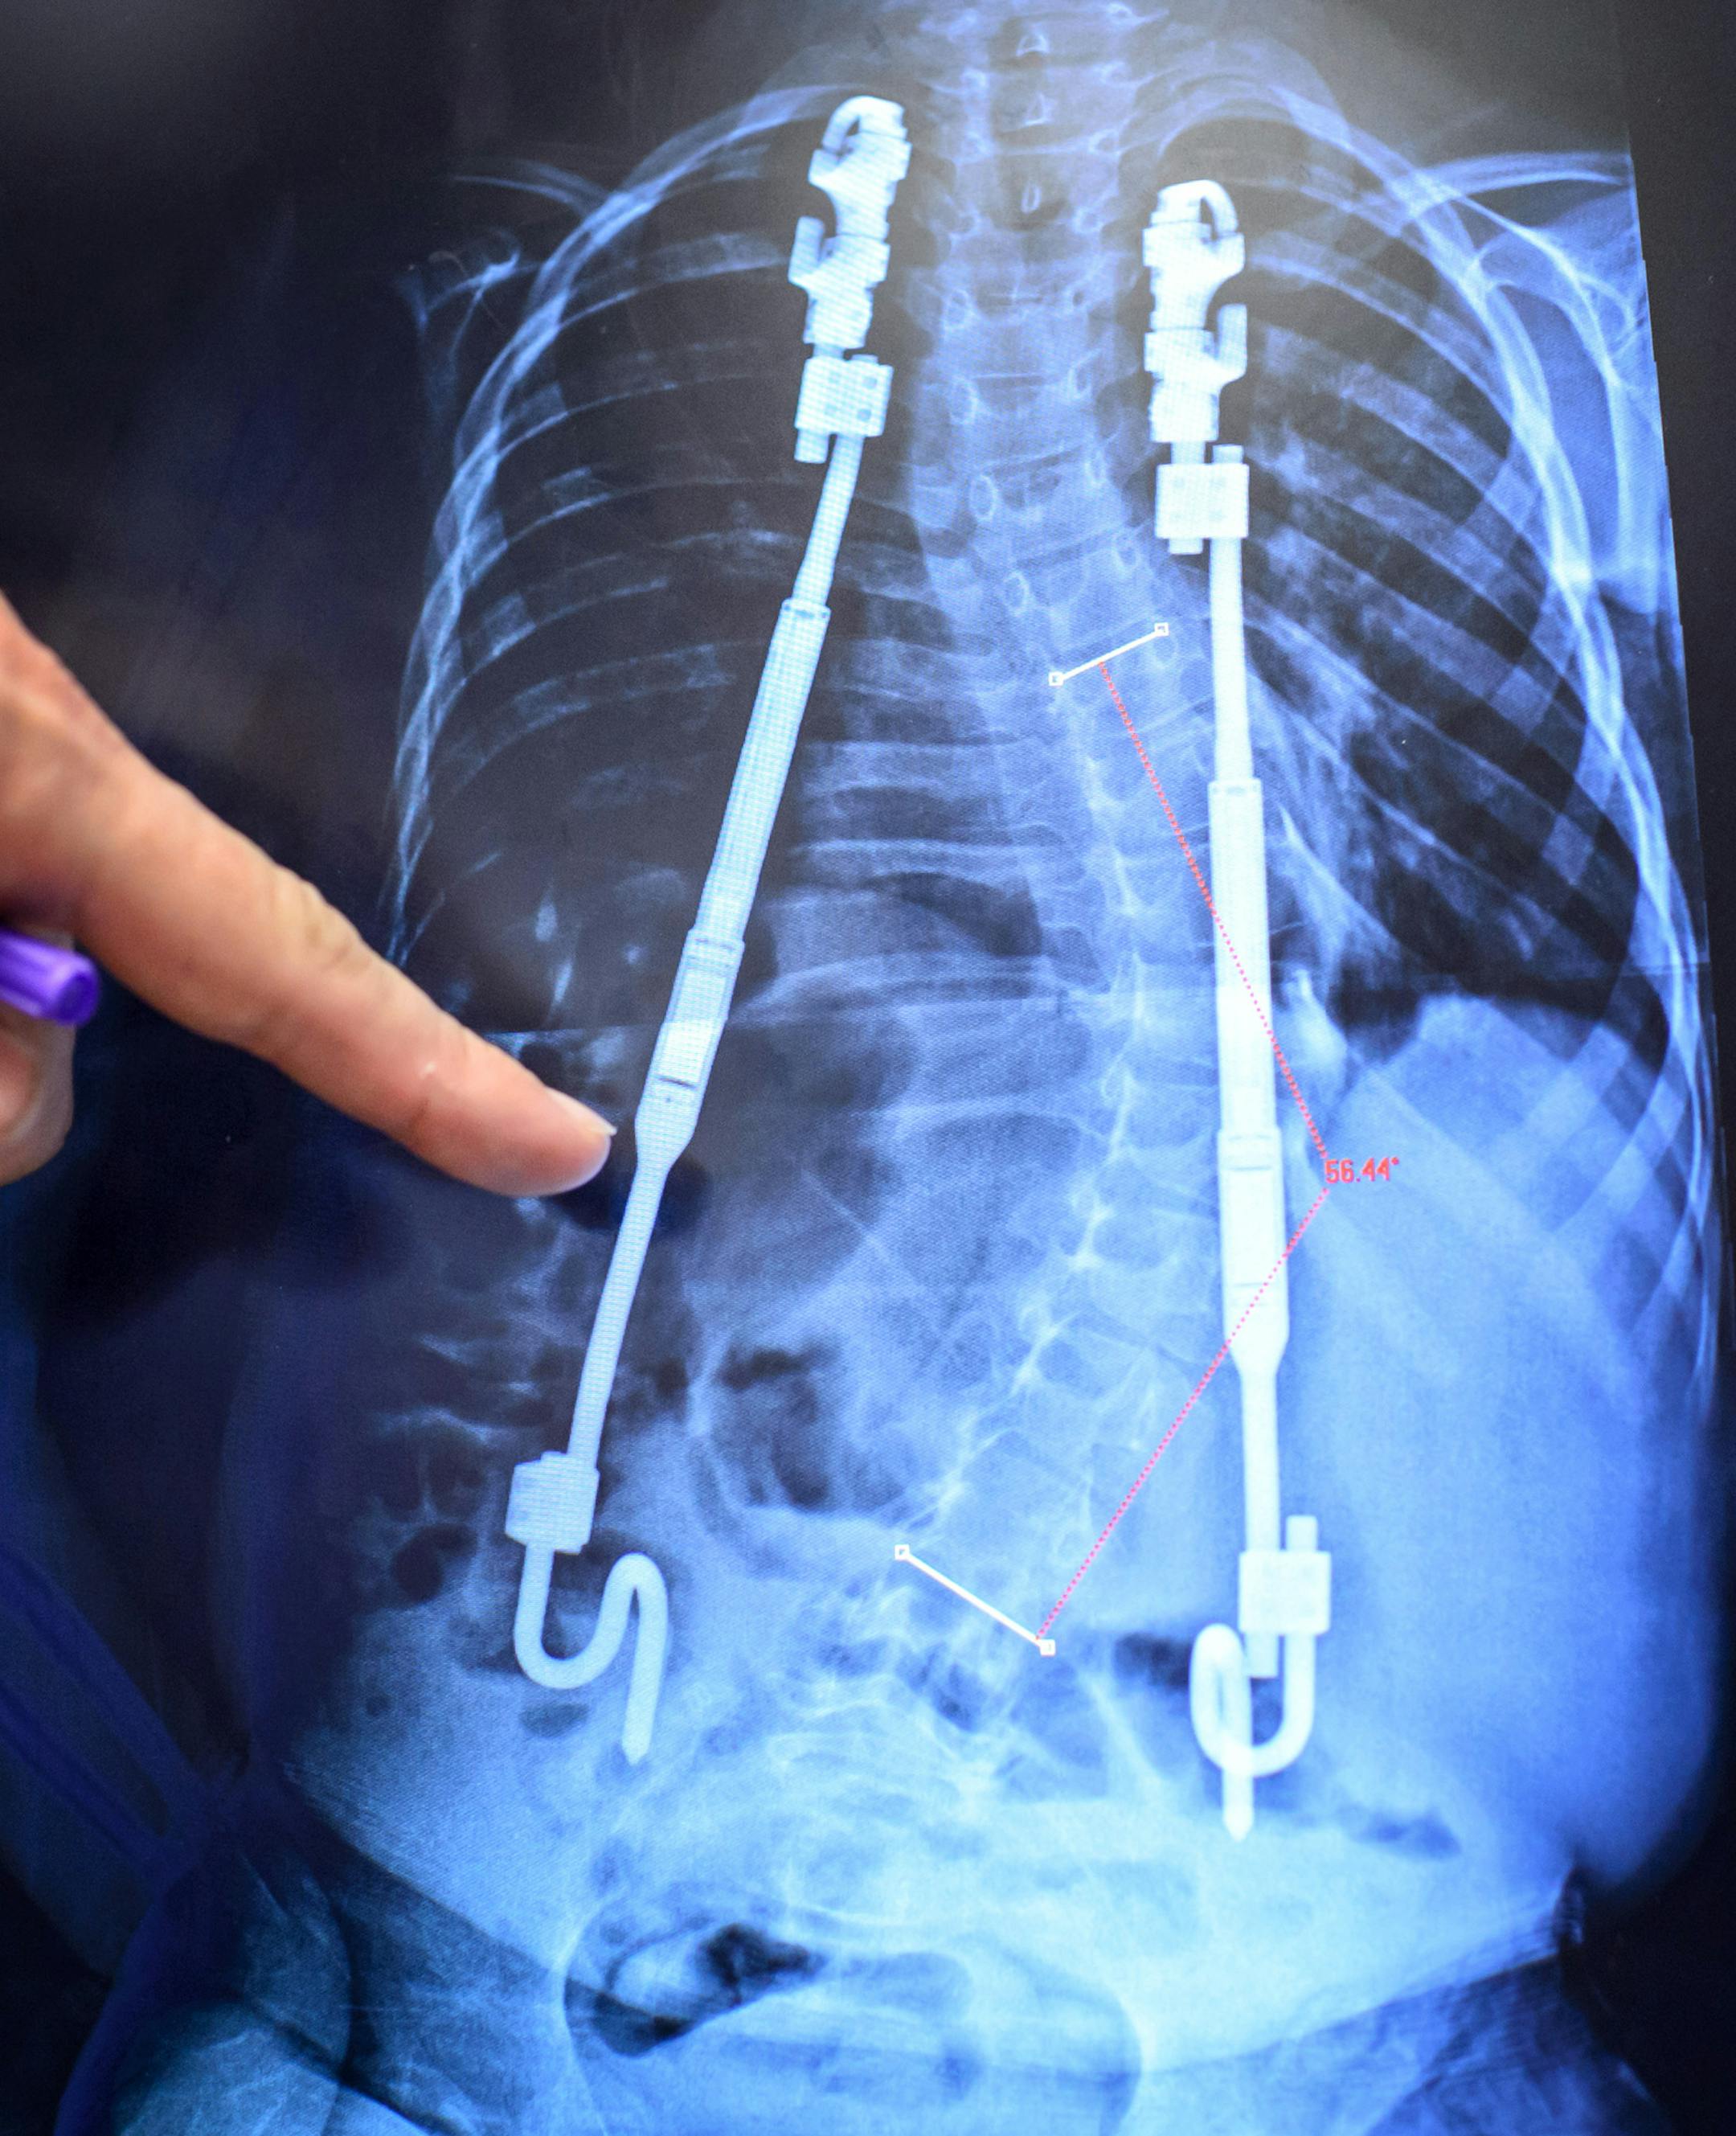

Dr. Tenner Guillaum pointed out where he had expanded the rods that are straightening Javier's spine by 6 millimeters The procedure was painless and lasted under a minute. ] GLEN STUBBE * gstubbe@startribune.com Wednesday, March 18, 2015 A new magnetically controlled device for young kids with severe scoliosis is preventing expensive and traumatic pediatric surgeries. The device is a spinal rod whose length doctors can expand using magnetic devices outside the skin. It replaces a solid rods used

Dr. Tenner Guillaume pointed where he had expanded the rods that are straightening Javier’s spine by 6 millimeters. The procedure was painless. (The Minnesota Star Tribune)

Growing-spine rods work by hooking around the ribs and the pelvic rim, underneath the skin, to create tension that corrects deformities without touching the vertebrae.

Javier Hruza had a quickly worsening 85-degree curve in his spine from neuromuscular scoliosis, which was caused by his spastic quadriplegic cerebral palsy. Such a severe curve can make breathing difficult, especially if the spine is twisting and deforming ribs, as ­Javier's was. Left untreated, curves of 100 degrees or more can lead to secondary ­problems that are associated with high mortality.